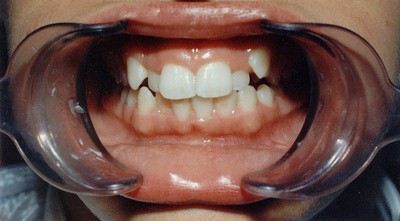

Клінічний випадок 1:

Катя І. 13 років

Діагноз: Дістопія іклів, піднебінні розташування бічних верхніх різців на верхній щелепі.

Лікування: У 13 років на брекет-системі можливе лікування навіть вираженої патології без видалення зубів.

Термін лікування: 18 місяців